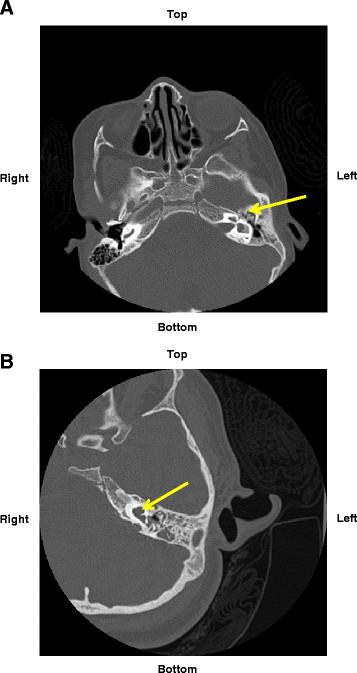

Goldenhar syndrome (GS) results from an aberrant development of the 1st and 2nd branchial arches. There is a wide range of clinical manifestations, the most common being microtia, hemifacial microsomia, epibulbar dermoids and vertebral malformations. We present two cases of GS and secondary immunodeficiency due to anatomical defects characteristic of this disorder. Case 1 (3-year-old female) averaged 6 episodes of sinusitis and otitis media per year. Case 2 (7-year-old female) also had recurrent otitis media, an episode of bacterial pneumonia, and 2 episodes of bacterial meningitis. Their immune evaluation included a complete blood count with differential, serum immunoglobulin levels and specific antibody concentrations, lymphocyte phenotyping, and mitogen and antigen responses, the results of which were all within normal ranges. Both children demonstrated major structural abnormalities of the inner and middle ear structures, retention of fluid in mastoid air cells, and chronic sinusitis by computed tomography. These two cases illustrate how a genetically-associated deviation of the middle ear cleft can cause recurrent infections and chronic inflammation of the middle ear and adjacent sinuses, even meninges, leading to a greatly reduced quality of life for the child and parents.

Goldenhar 综合征(GS)是由第一和第二鳃弓的异常发育引起的。其临床表现广泛,最常见的是小耳畸形、颜面半侧短小畸形、眼外皮肤肿块和椎体畸形。我们报告了两例 GS 病例,由于该疾病的解剖缺陷导致继发免疫缺陷。病例 1(3 岁女性)平均每年有 6 次鼻窦炎和中耳炎发作。病例 2(7 岁女性)也有反复发作的中耳炎、细菌性肺炎和 2 次细菌性脑膜炎。她们的免疫评估包括全血细胞计数和分类、血清免疫球蛋白水平和特异性抗体浓度、淋巴细胞表型、有丝分裂原和抗原反应,结果均在正常范围内。这两个孩子都表现出中耳结构的主要结构异常、乳突气房积液和慢性鼻窦炎,通过计算机断层扫描显示。这两个病例说明了中耳裂隙的遗传相关偏离如何导致中耳和相邻鼻窦,甚至脑膜的反复感染和慢性炎症,从而导致儿童及其父母的生活质量大大降低。